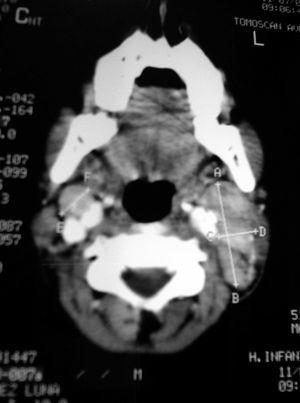

Caso 1. Niño de 12 años, que presenta fiebre de 10 días de evolución, y tumoración cervical dura-elástica, sensible a la palpación, de 3 × 4 cm, acompañada de hepatoesplenomegalia, astenia y exantema maculopapuloso. Pruebas complementarias: 4,67 × 109 leucocitos, con 2,87 × 109 neutrófilos. LDH 721 Ul/l. PCR 85 mg/l. VSG 59 mm/h. Tomografía por emisión de positrones (PET): afectación linfática cervical y supraclavicular. TC: conglomerados adenopáticos, con realce periférico y zonas hipodensas centrales (fig. 1). Estudio anatomopatológico: linfadenitis necrosante, compatible con enfermedad de Kikuchi-Fujimoto. Inmunohistoquímica: numerosas células dendríticas plasmocitoides (CD 123, TCL 1), confirmando el diagnóstico.

Figura 1.TC. Conglomerados adenopáticos con imágenes sugestivas de necrosis en su interior.